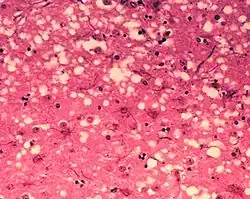

Действие на клетки

Диапазон структурных и биохимических эффектов, оказываемых вирусом на инфицированную клетку, очень широк[118]. Они называются цитопатическими эффектами[119]. Большинство вирусных инфекций приводят к гибели клеток-хозяев. Причинами гибели могут быть лизис клетки, изменения клеточной мембраны и апоптоз[120]. Часто причиной гибели клетки является подавление её нормальной активности белками вируса, не все из которых входят в состав вирусной частицы[121].

Некоторые вирусы не вызывают никаких видимых изменений в поражённой клетке. Клетки, в которых вирус находится в латентном состоянии и неактивен, имеют мало признаков инфекции и нормально функционируют[122]. Это является причиной хронических инфекций, и вирус при них может никак себя не проявлять многие месяцы или годы. Так часто бывает, например, с вирусом герпеса[123][124]. Некоторые вирусы, например вирус Эпштейна — Барр, могут вызывать быстрое размножение клеток без появления злокачественности[125], в то время как другие, такие как папилломавирусы, могут вызвать рак[126].